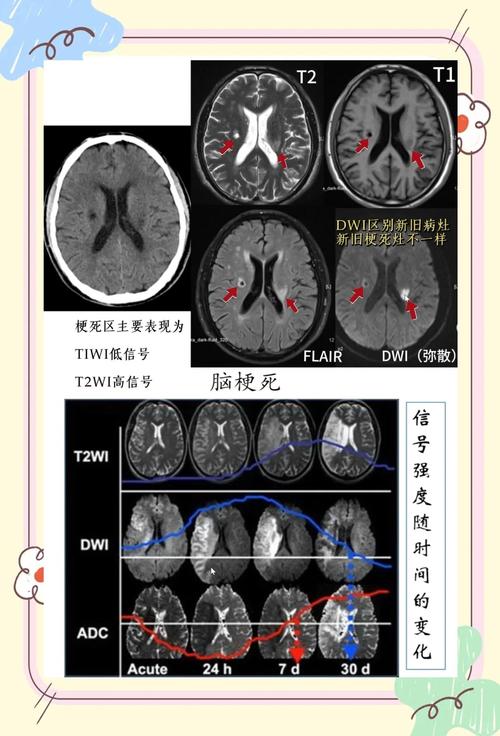

- CT通常是阴性的! 这是最大的陷阱,此时诊断主要依靠临床症状和MRI-DWI(弥散加权成像),DWI对早期缺血非常敏感。

- 对于怀疑急性脑梗死的患者,如果CT结果阴性,强烈建议立即进行头颅MRI检查,特别是DWI序列,以明确诊断并指导治疗(如静脉溶栓)。